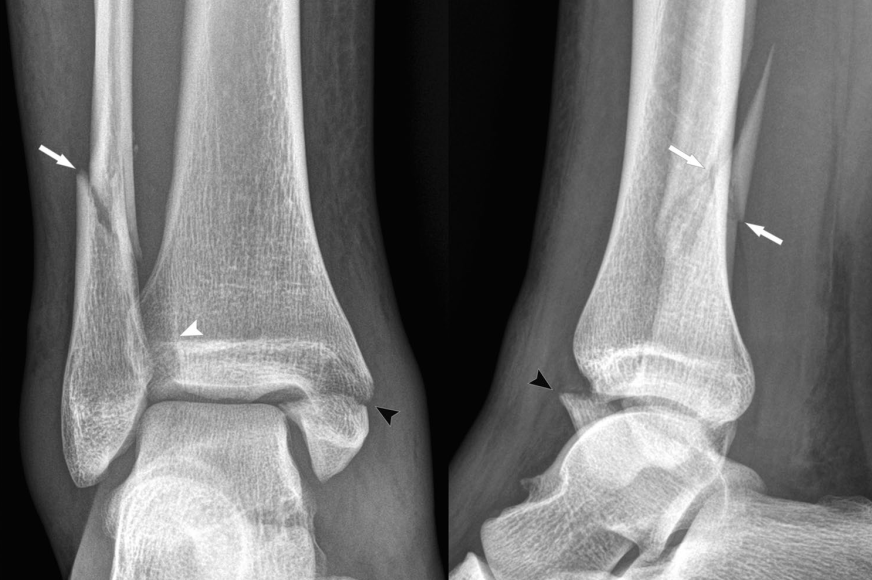

然而,在临床实际应用中,常规X线摄片仅能明确骨折情况,对下胫腓韧带损伤、外侧韧带、内侧三角韧带的损伤不能直接判断,需结合损伤机制推断,为避免漏诊韧带损伤,有学者提出了“损伤环”理念,旨在通过“环”的损伤顺序,推断合并的韧带损伤。

1. 旋后外旋损伤

对踝关节损伤机制的判断,首先观察外踝骨折线形态。对前低后高型外踝骨折线,提示旋前外旋损伤。依据“损伤环”理念,下胫腓前韧带、外踝、下胫腓后韧带、内踝组成的环依次损伤,分别标为“1-4”,后方损伤提示必定存在前结构的损伤。